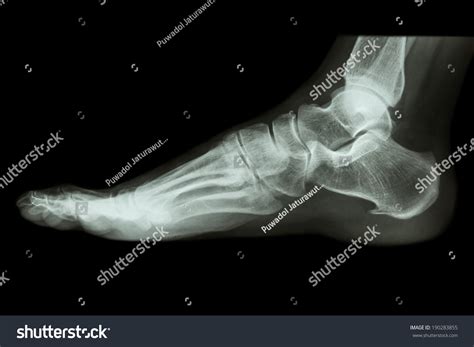

The patient is positioned on the X-ray table, and the foot is placed in a specific position to capture the desired views. Common views include:

• Anteroposterior (AP) view: Shows the foot from the front.

• Lateral view: Shows the side of the foot.

• Oblique view: Shows the foot at an angle.

Interpreting a Normal Foot X Ray involves a thorough examination of the images to ensure that all structures appear normal. Key areas of focus include:

Bones

The bones of the foot, including the tarsals, metatarsals, and phalanges, should be clearly visible and aligned properly. Any fractures, dislocations, or deformities would be immediately apparent.

Joints

The joints between the bones should be smooth and well-defined. Any signs of arthritis, such as bone spurs or joint space narrowing, would indicate an abnormality.

Soft Tissues

While X-rays primarily show bones, they can also provide some information about soft tissues. Any swelling, inflammation, or foreign objects would be noted.